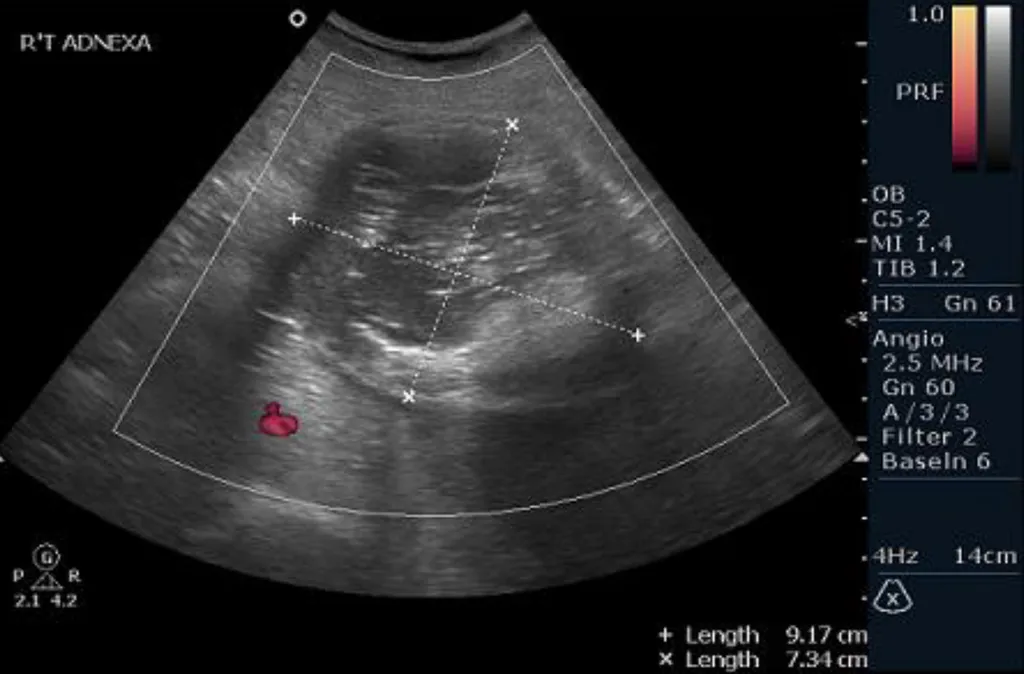

【114-2 醫學(六) 第48題】30 歲女性,在健康檢查時,意外在骨盆超音波下,發現如圖所示之腫塊,最有可能的診斷為何?

詳解

破題關鍵

這張骨盆超音波影像顯示一個右側卵巢的複雜性囊腫,其內部有明顯的混合回音,包含高回音的實質成分伴隨後方聲影,這是畸胎瘤(dermoid cyst)的典型特徵,常被稱為「冰山一角」(tip of the iceberg)或「皮樣栓」(dermoid plug)徵象。

選項拆解